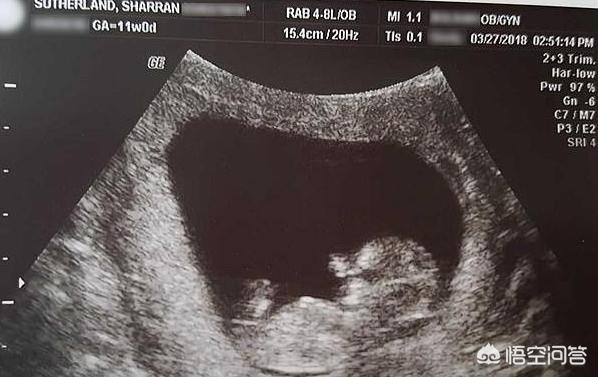

这通过B超可以看出来,有经验的医生看了女性子宫的B超,就知道是否怀孕过,是否做过流产,是否分娩过。人流手术是刮宫,这让子宫壁变薄。